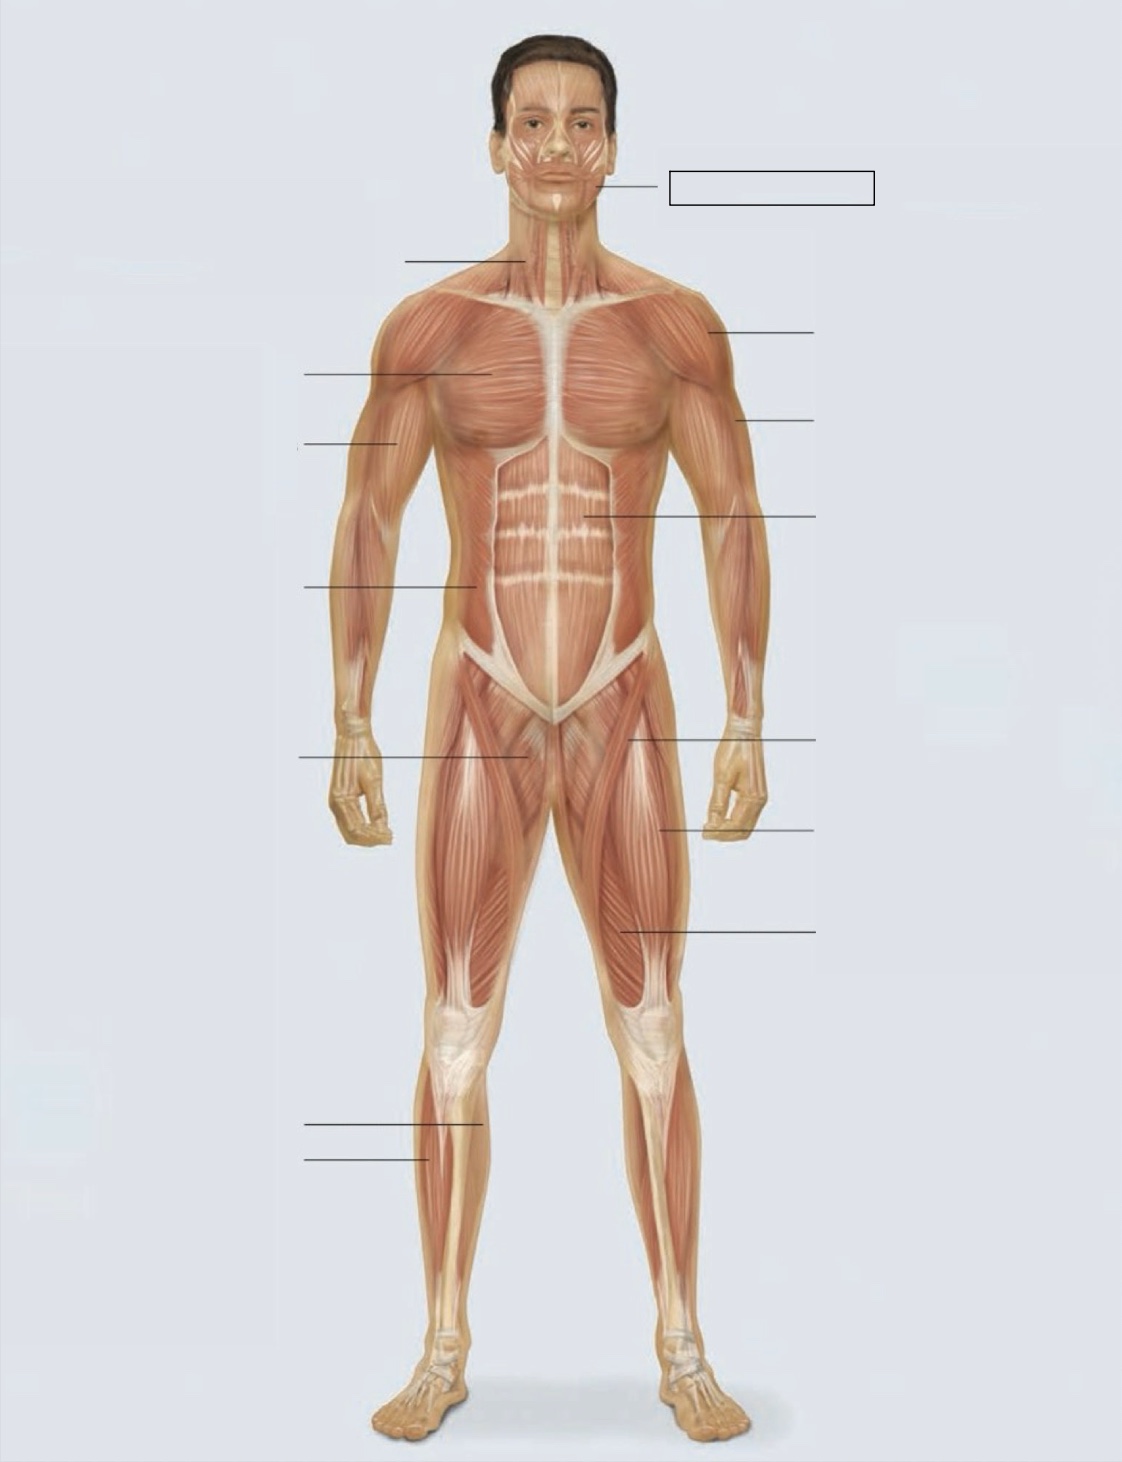

masseter

deltoid

triceps

rectus abdominis

sartorius

quadriceps femoris